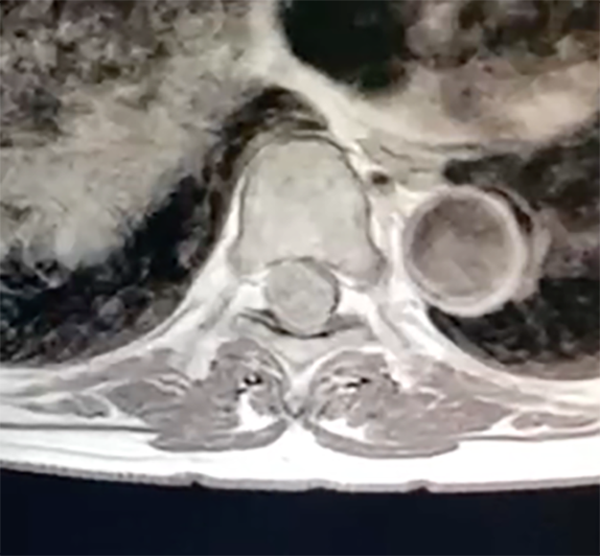

Se realiza RM de columna con contraste, en la que se evidenció una formación expansiva intradural-extramedular con base de implantación dural en el sector dorso-lateral derecho del nivel T8. Presentaba señal hipointensa en T1, T2 y STIR, presentando realce homogéneo tras la administración de contraste endovenoso, midiendo aproximadamente 19 mm x 17 mm x 13 mm (figura 1 y 2), generando compresión del cordón medular. Hallazgos compatibles con probable meningioma. Se puso en plan quirúrgico para exéresis tumoral mediante abordaje MISS.

Fig. 1: RMN de columna dorsal con contraste que evidencia lesión expansiva en D8.

Fig. 2: Corte axial de misma RMN con medula completamente desplazada en sentido anterolateral izquierdo.